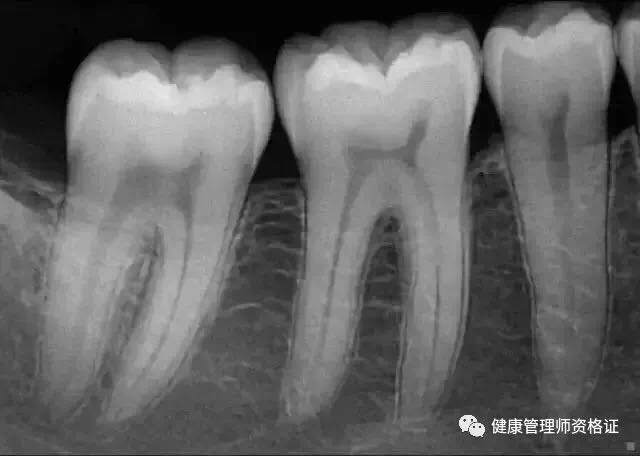

(3)小牙片

以檢查單顆牙齒為目的,一般圖像上可顯示2~4顆牙齒,能觀察到牙根的情況,所以牙醫們要檢查單顆牙齒時,往往會選擇拍攝小牙片。